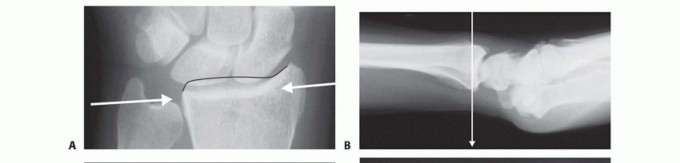

FIG 4 • A. Positioning for standard lateral radiography. B. Standard lateral radiograph. C. Positioning for 10-degree lateral radiography. D. Ten-degree lateral radiograph. Note the improved visualization of the articular surface of the base of the scaphoid facet and the entire lunate facet. Injuries from a high-energy mechanism present as complex comminuted fractures of the articular surface with extension into the radial/ulnar shaft ( FIG 3I).